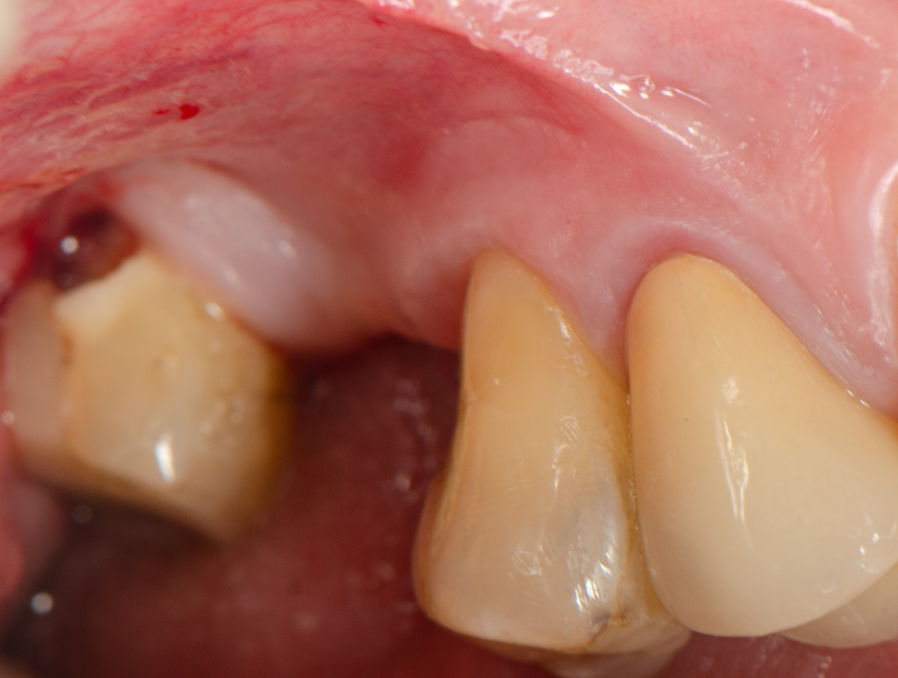

Técnica cirúrgica

Sob anestesia local, realizou-se incisão crestal na área edêntula do dente 16. O sítio foi marcado com broca lança e fresado conforme protocolo Implacil Osstem para implantes de 4,0 mm. O implante Maestro Superiore 4,0 × 9 mm foi instalado, apresentando torque progressivamente elevado até a posição final, com plataforma 2 mm infraóssea. O torquímetro registrou 50 Ncm, confirmando excelente estabilidade primária, condição favorável para carga precoce ou imediata, em linha com a literatura que destaca a alta fixação inicial dos implantes Maestro sem comprometer o osso circundante.